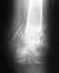

Перечисленные медикаменты в этой ситуации бесполезны. В 23 года просто нет тех метаболических нарушений, на которые они направлены.

Здесь нужно сделать межвертельную вальгизирующую остеотомию. Вряд ли в Пятигорске эти операции на потоке.